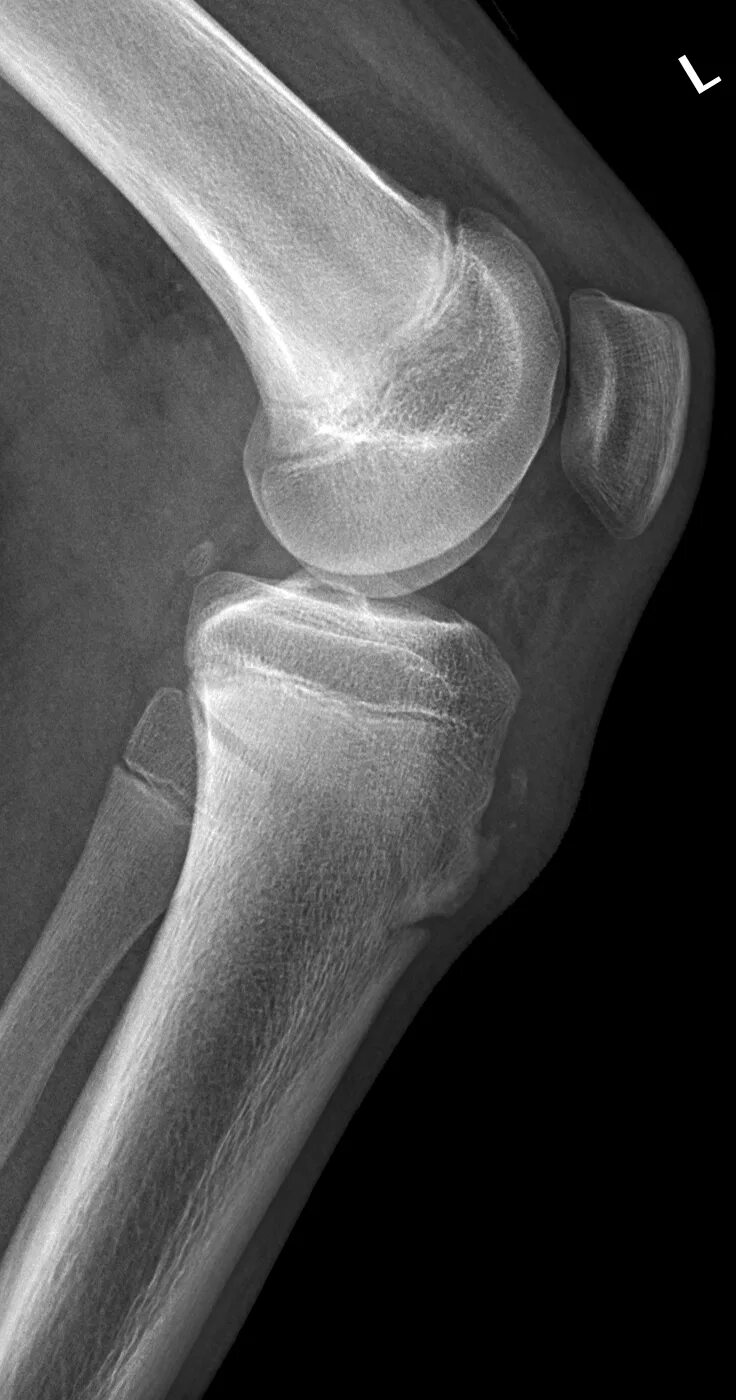

Синдром осгуда шляттера